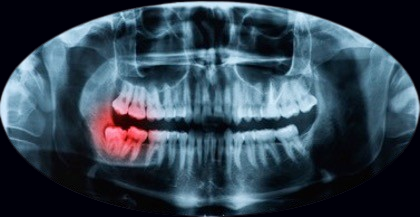

La radiographie est la forme d'imagerie médicale la plus ancienne et la plus fréquemment utilisée. Les rayons X peuvent produire des images diagnostiques du corps humain sur film ou numériquement. Elle analyse les parties solides du corps c'est-à-dire les os, les articulations, la dentition. La radiographie standard correspond à la radiographie d'une région d'intérêt dont la réalisation obéit à un protocole reconnu de manière internationale. Elle permet d'obtenir des images de différentes parties du corps sous des angles différents.